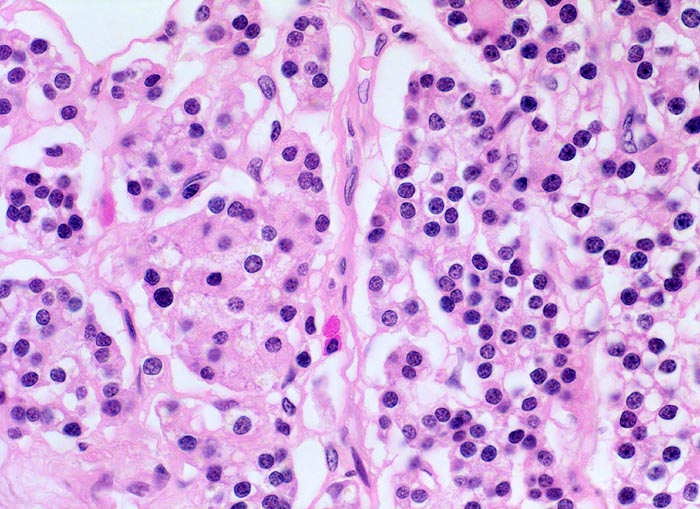

• Hyperplasie lipidarmer Hauptzellen.

• Areale mit oxyphilen Zellen.

• Verminderter Fettgehalt (<<35%). Für normale Nebenschilddrüsen gilt: